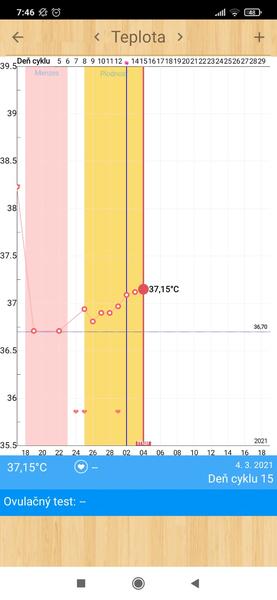

Grafy bazálnej teploty

Ak meriate bazálnu teplotu a zapisujete si hodnoty do grafov, ste na správnom mieste. Poradíme, pomôžeme, podporíme.

Grafy si môžete vytvárať na nasledovných stránkach:

www.fertilityfriend.com

www.womenzone.cz

www.wunschkinder.net

Všetko o meraní BT a jednotlivých programoch na vytváranie grafov nájdete tu: http://merenibt.xf.cz/index2.html